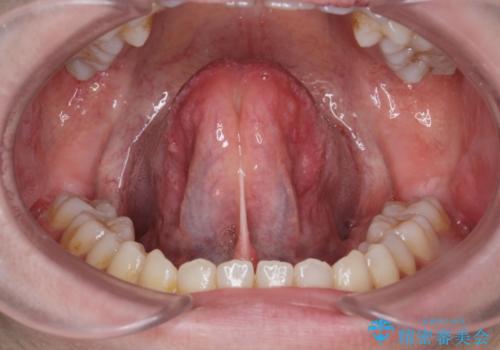

[ 舌の小帯の形成術 ] 滑舌を改善したい

担当医 大元洋佑

![[ 舌の小帯の形成術 ] 滑舌を改善したいの症例 治療前](https://seimitsushinbi.jp/wp/wp-content/uploads/2023/10/IMG_7222-500x350.jpg?v=1697768320)

![[ 舌の小帯の形成術 ] 滑舌を改善したいの症例 治療後](https://seimitsushinbi.jp/wp/wp-content/uploads/2023/10/IMG_7670-500x350.jpg?v=1697768329)